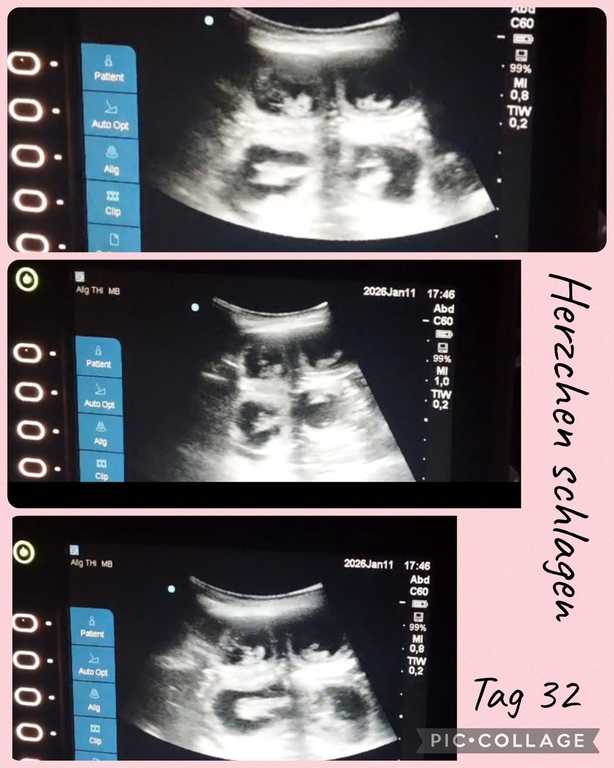

Fae ist trächtig und bekommt Mitte Februar ihren erste Wurf mit fast 3 Jahren. Fae hat vor einemb3/4 Jahr ein HUS und zwei Tage vor Belegung eine auskultation HG 0. Ihre Mutter ist die wundervolle Isabella Marie genannt 8 Jahre alt und in Rente seid 1,5 Jahren .Sie lebt bei uns . Mama Marie hat eine wundervolle Ahnentafel ,ihr Vater Faes Opa ist fast 15 Jahre alt geworden. Tolle alte Linien in der AT.

Seid Sonntag sind wir wieder glückliche Besitzer eines Ultraschallgerätes. Ein wunderbares leichtes und auch tragbares US. Durch liebe Menschen hatten wir glück dieses noch nicht so alte Ultraschallgerät zu bekommen. (War vor kurzem noch im Einsatz im KH Notaufnahme). Danke Pelin & Hanno